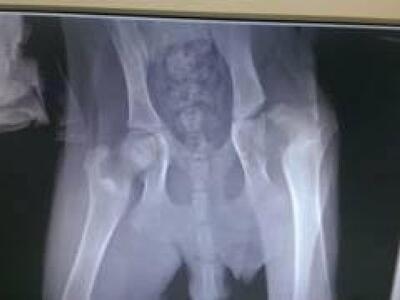

Μεταφέρθηκε στον κτηνίατρο για εξετάσεις όπου διαπιστώθηκε πως πρέπει να χειρουργηθεί και να γίνει αφαίρεση κεφαλής μηριαίου και να γίνει καινούργια άρθρωση με ό,τι έχει απομείνει. Αν ενδιαφέρεται κάποιος να βοηθήσει τη σκυλίτσα με οποιοδήποτε τρόπο να επικοινωνήσει με το 6974557706.